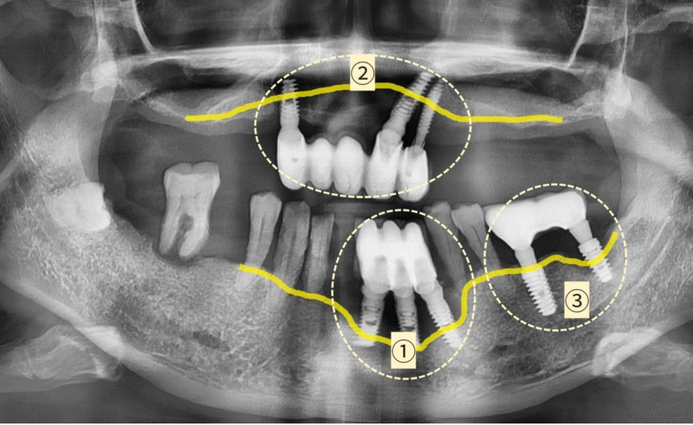

Tôi sẽ gợi ý cho bạn ở hình bên dưới.

(Đường liền màu vàng là đường xương nướu nâng đỡ răng và chân răng implant)

Như đã giải thích ở trên, cấy ghép ① và ②

có xương nướu đã tan chảy hơn 1/3 chiều dài của trụ implant cần phải được loại bỏ.

Ở phần ① và ②, như trong ảnh,

độ sâu của xương ổ răng bị mất sâu và lan rộng,

do đó thay vì trồng lại implant ở khu vực đó,

implant được trồng ở xương ổ răng xung quanh tương đối khỏe mạnh

và cầu răng implant được kết nối . Bạn có thể lên

kế hoạch cho phương pháp điều trị ‘cầu răng implant’.

Trong trường hợp cấy ghép số ③,

có thể xây dựng kế hoạch điều trị để ngăn ngừa tình trạng

viêm nặng hơn và mất xương nướu thêm thông qua phẫu thuật thẩm mỹ

Implant mà không cần tháo implant đã cấy và để cứu implant hiện tại càng nhiều càng tốt.